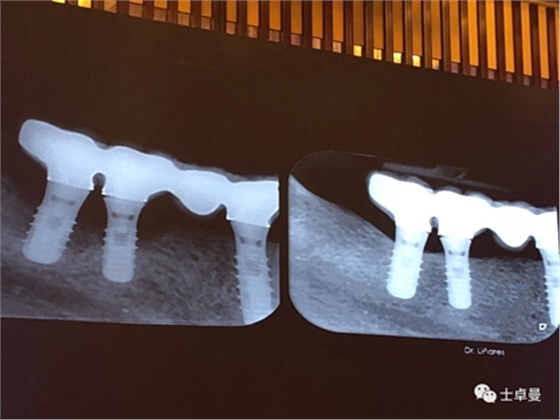

手術(shù)方式治療則需通過翻瓣清潔種植體及修復體上菌斑牙石,推薦在此過程中使用士卓曼鈦刷,因為該鈦刷不會損傷種植體表面細微結(jié)構(gòu)。之后進行植骨蓋膜來促進種植體周圍吸收部分的骨的重建。